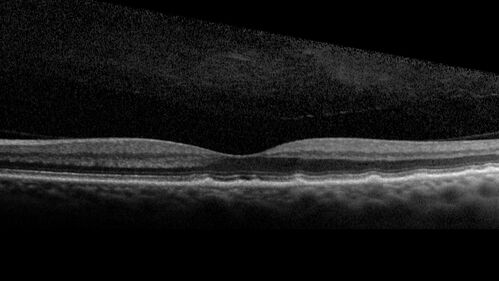

Large and Extensive Macular Drusen

64 year old female with 20/25 vision taking vitamins in for a checkup.